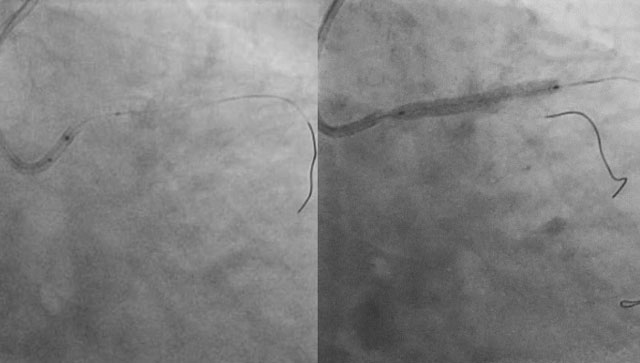

Coronary perforation

Perforations can be life threating and need to be managed correctly. Discover this section presented by O. Muller, P. Calvert, M. Haude, E. Eeckhout and A. Lerman.

Consult the complications section on Coronary perforations or visit the latest resource which explains how to manage embolised device complications like a Coronary implant loss, in particular Coronary stent dislodgement, lost scaffold, guidewire loss and balloon fracture.